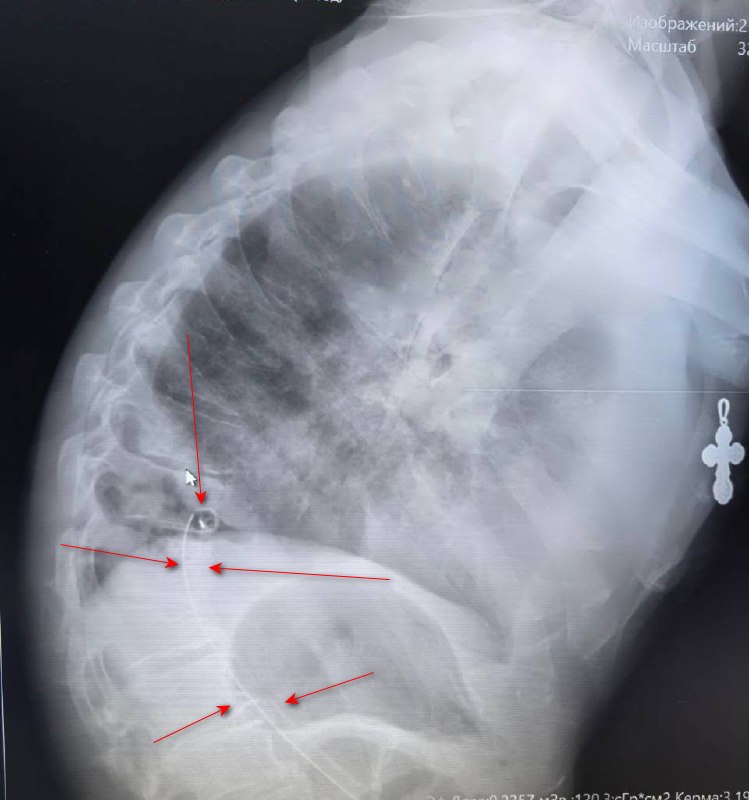

Добрый день, справа уменьшение объёма S3, инфильтрация,   подозрение на ЗНО бронха?

Пневмония?По боковой проекции видна праволока- что это? Это не из мест лишения свободы?

Видно в обеих проекциях. Это не проволока, а дренаж. Странно, что так низко. Гипоэктаз, если и есть, то в средней и нижней долях. S3 не при делах.  Пневмнония с признаками деструкции.

Был ли пациент оперирован?. Необходимо со снимками давать больше информации о пациенте: возраст, клиника, анамнез, архив, если есть. По голым снимкам кто ж Вам правду скажет?

Думаю, это лучше спросить у urievich. Пациент ему ближе к телу. А у нас информации- ноль. Меня удивило, что дренажная трубка так низко.

Удалось уточнить, в мае на КТ выставлено центральное ЗНО правого легкого, ателектаз правого легкого. Мы можем достоверно сказать о наличии гидроторакса?

На представленных снимках признаков гидроторакса не нахожу.

Я бы не исключал явления гидроторакас справа( угол наружного синуса тупой).